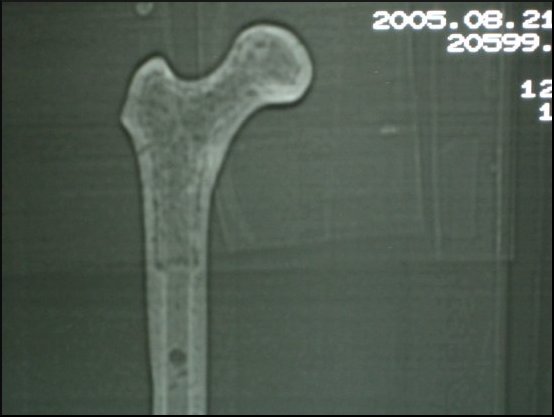

Dobierając skład chemiczny i strukturę materiału kompozytowego, z którego wykonujemy modele przeznaczone do szkoleń, główny nacisk położyliśmy na dokładne odtworzenie właściwości naturalnej kości. W tym celu poddaliśmy kość różnorodnym badaniom. Tą samą technikę zastosowaliśmy badając modele z materiałów kompozytowych.